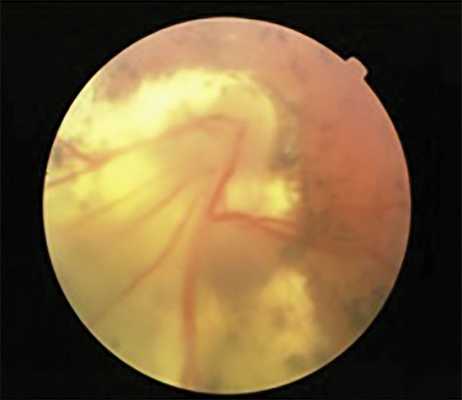

При дальнейшем прогрессировании процесса в ранние сроки (36—42 нед гестации) развивается отслойка сетчатки «воронкообразной» или «вулканообразной» конфигурации, при которой отслаивается васкуляризированная сетчатка в первой зоне в виде купола, закрывающая ДЗН (рис. 5). Рисунок 5. «Вулканообразная» отслойка сетчатки в первой зоне.